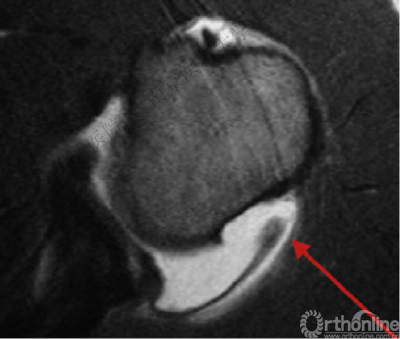

盂肱下韧带肱骨侧止点撕裂

3.反Hill-Sachs损伤合并反Bankart损伤被Moroder命名为“双极损伤”。

4.δ角是发生肱骨头后脱位所需的肩关节内旋角度,在双极损伤中δ角减小,所以在双极损伤中,即使较轻的反Hill-Sachs损伤也需要修复。